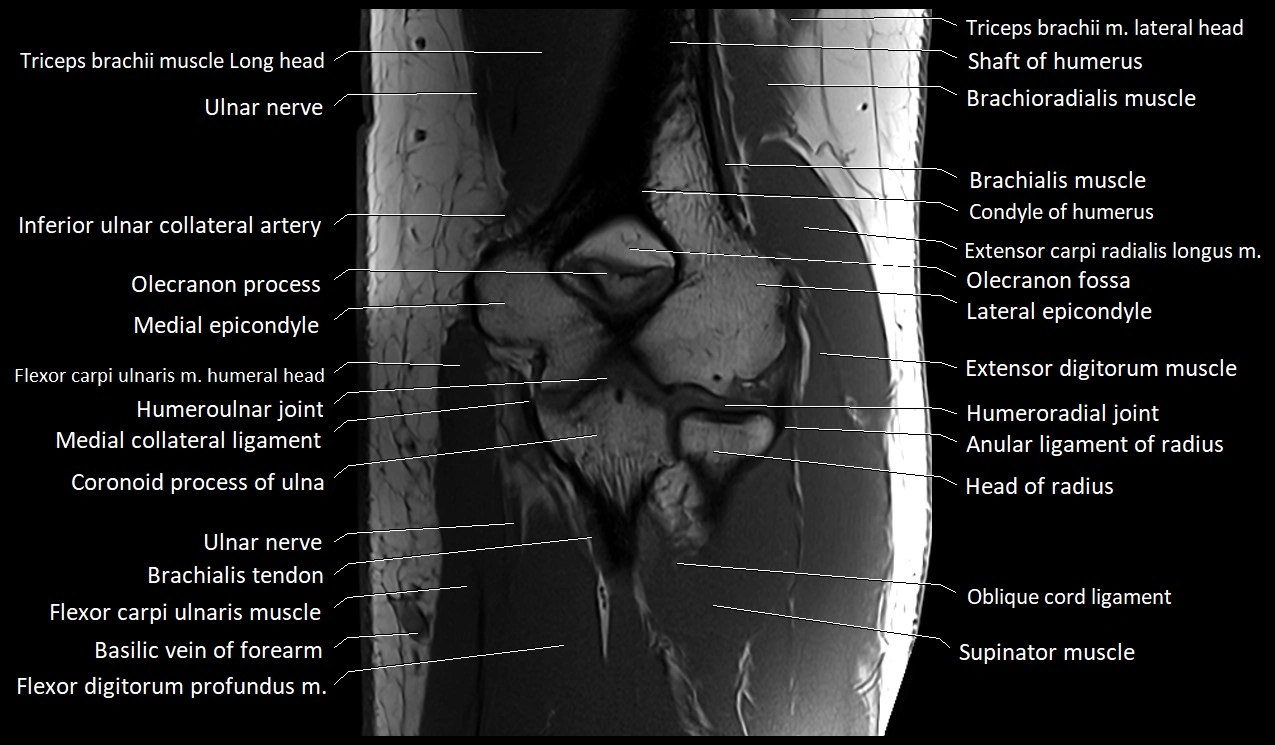

MRI image

image